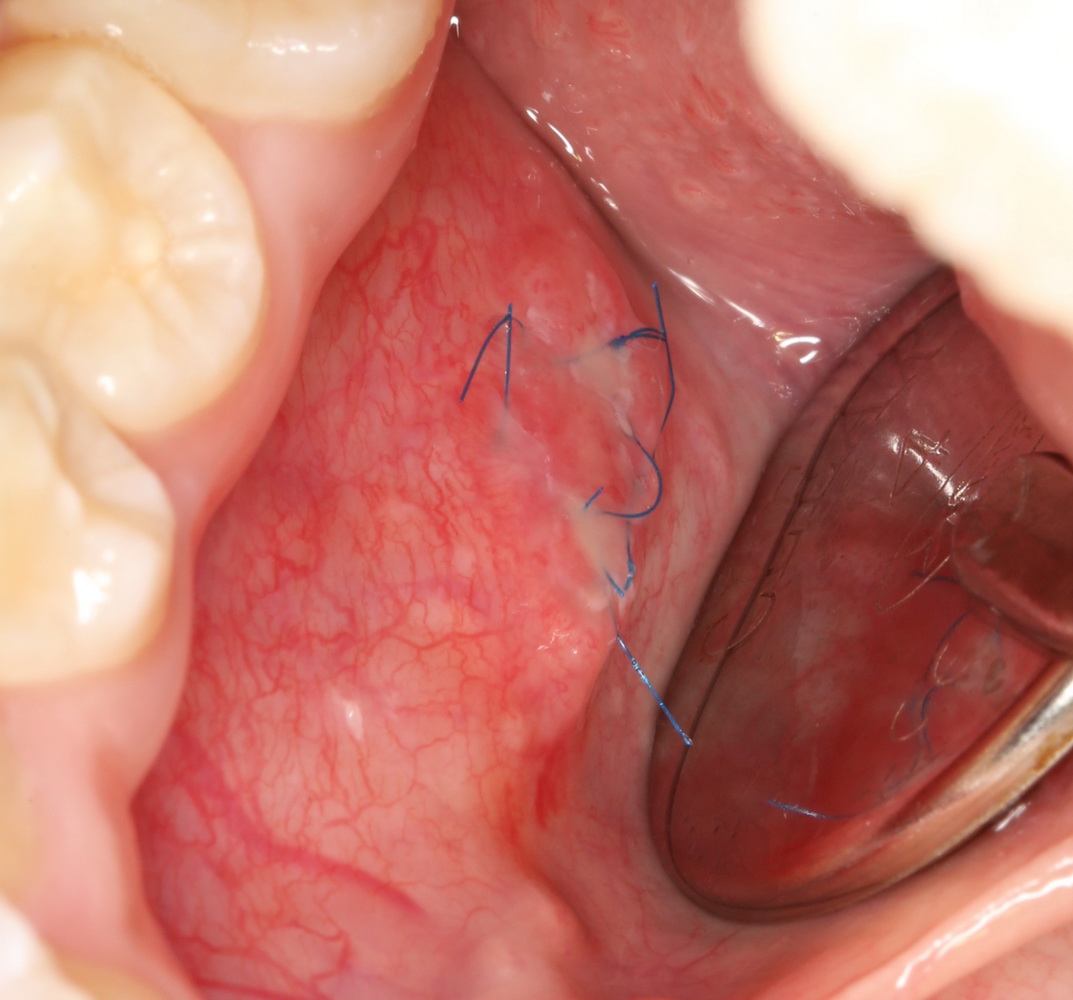

Такую работу я покажу на примере. Ко мне обратилась маленькая пациентка, девочка восьми лет с жалобами на появление новообразования под языком:

До этого они с мамой уже побывали в крупном государственном лечебном учреждении, где им поставили диагноз «ранула» и, по старой советской традиции, направили на госпитализацию и кучу анализов. Еще попутно напугали всякими страшилками, вроде того, что написал про инфекцию выше. В общем, мама девочки задумалась и обратилась ко мне.

Мы побеседовали с девочкой, она согласилась на местную анестезию. И, должен отметить, вела себя лучше некоторых взрослых.

Всю операцию мы проводили под оптическим увеличением — так проще и лучше видно. А нормальный обзор в подобном случае — это наше всё.

Сначала аккуратно удаляется верхняя часть часть кисты, ее крыша. Для этого киста рассекается ножницами, удаляется ее содержимое, а образовавшийся мешок просто отрезается почти заподлицо: